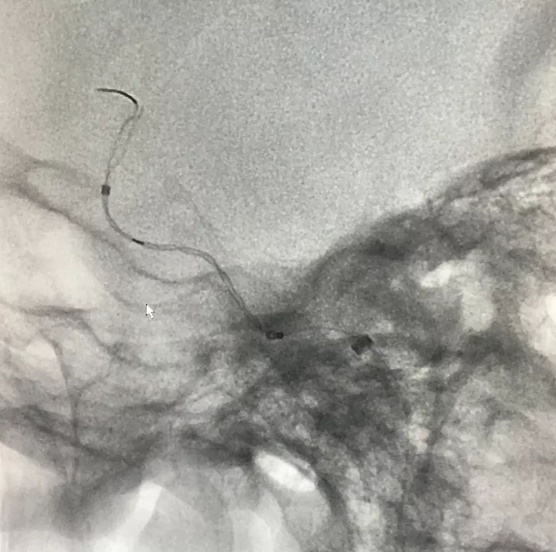

Tubridge®血管重建装置专用支架导管T-track到位,引入4.0mm*30mm支架。

准确定位后,锚定支架头端,缓慢推送支架的同时控制支架张力,顺利释放支架。

为进一步确保Tubridge®血管重建装置完美贴壁,上J型导丝支架内“按摩”。

多角度确认支架已完全贴壁。